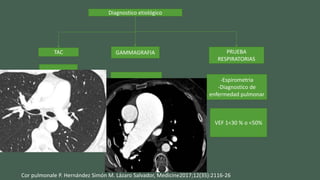

Diagnostico etiológico

TAC GAMMAGRAFIA PRUEBA

RESPIRATORIAS

-Diametro

arterias

pulmonares

-Trombosis

Tromboembolismo

pulmonar

-Espirometria

-Diagnostico de

enfermedad pulmonar

VEF 1<30 % o <50%

Cor pulmonale P. Hernández Simón M. Lázaro Salvador, Medicine2017;12(35):2116-26